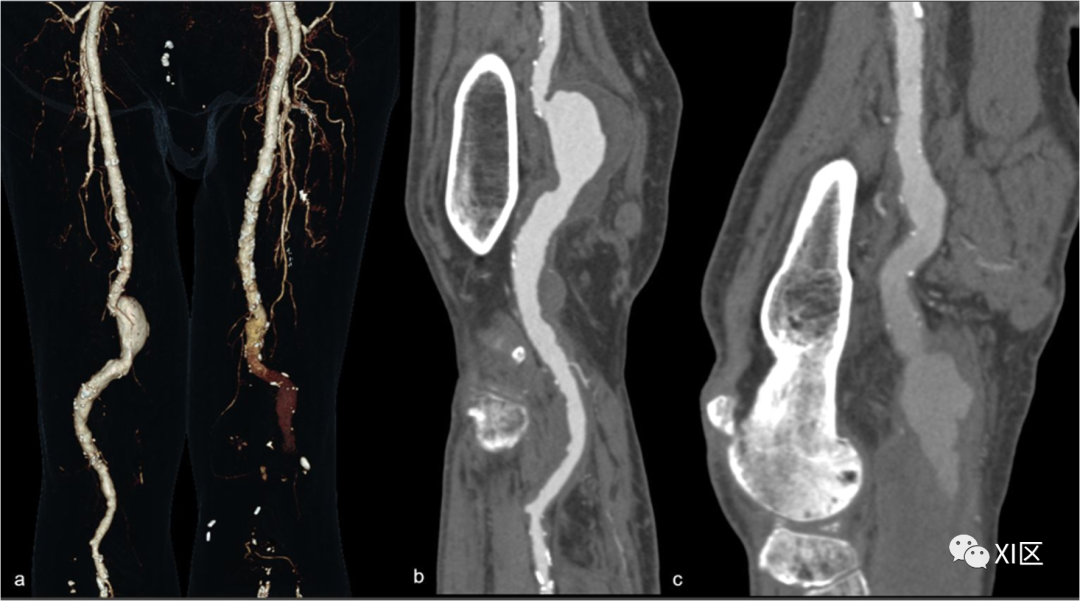

腘动脉瘤包括腘动脉的局灶性扩张,其直径大于对侧腘动脉或股浅动脉的直径,在高达75%的病例中为双侧受累(图6)。

图6 双侧腘动脉瘤。75岁男子出现左室缺血症状。VRT重建显示双侧腘动脉瘤(a)。右侧动脉瘤的CPR重建显示了巨大的贴壁血栓。c 左侧动脉瘤的CPR重建显示动脉瘤的很大一部分没有被造影剂填充。

与这些动脉瘤相关的并发症包括血栓形成、壁血栓栓塞和破裂。CTA可以检测动脉瘤的特征,包括口径、颅尾延伸、壁血栓的形态、流出的解剖结构,并确定不能用DSA评估的造影剂填充的腔内部分,以便进行正确的治疗管理。